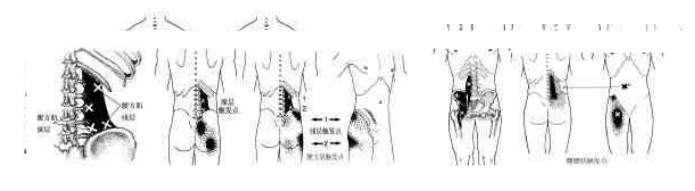

1.1 胸锁乳突肌:该肌有七个疼痛触发点,浅层(胸骨头)有四个,深层(锁骨头)有三个,其牵涉疼痛的位置见图一。

1.2 斜方肌:该肌也有七个疼痛触发点,其牵涉疼痛的位置见图一。颈角处的触发点(TP1)可引起头颞部的牵涉痛;TP2和TP3向上引起枕根部的牵涉痛;TP4引起C7处及其周围的牵涉痛;TP5引起肩胛间的牵涉痛;TP6引起肩周牵涉痛;TP7引起手臂部的牵涉痛。

1.3 颈后肌:其肌群是由多块小肌所组成,可以在颈后部任何一个位置形成疼痛触发点引起头颞部和枕部的牵涉痛(图二)。

1.4 头夹肌和颈夹肌:颈夹肌有一个疼痛解发点可引起头顶部的牵涉痛(图二)。颈夹肌有二个疼痛触发点,上点是引起耳部周围和太阳穴牵涉痛,下点引起颈角后部牵涉痛(图二)。

1.5 枕下肌(头上、下斜肌和头直肌): 各肌仅有一个疼痛触发点,其牵涉痛位置见图二

2.1 竖脊肌和多裂肌触发点位置(图三): 竖脊肌在下背部和腰部分为内侧群和外侧群,外侧群触发点的位置常在12胸肋处,内侧群触发点10-11胸肋和腰1水平。多裂肌触发点多在腰2、骶1和骶3-4水平。

2.2 腰方肌和髂腰肌触发点位置(图四):腰方肌分深和浅两层,各有两个常见

图四. 腰方肌和髂腰肌常见触发点位置和各点多发的特定牵涉痛范围。叉为触发点位置,点为牵涉痛的范围,密集点示疼痛较重的部位。

触发点,常引起大腿后部疼痛。髂腰肌常有3个触发点,常引起大腿前部的疼痛。

图五. 臀大、中、小肌常见触发点位置和各点多发的特定牵涉痛范围。叉为触发点位置,点为牵涉痛的范围,密集点示疼痛较重的部位。

2.3 臀大肌和臀中肌触发点位置(图五):该2肌常引起下肢的牵涉痛,一般都有3个触发点。各点的触发点位置和特定牵涉痛范围见图五。

2.4 臀小肌和梨状肌触发点(图六):两肌均有更远处的牵涉痛,如果合并有其它肌触发点疼痛,常需要与椎间盘脱出症和椎管狭窄症做鉴别诊断。